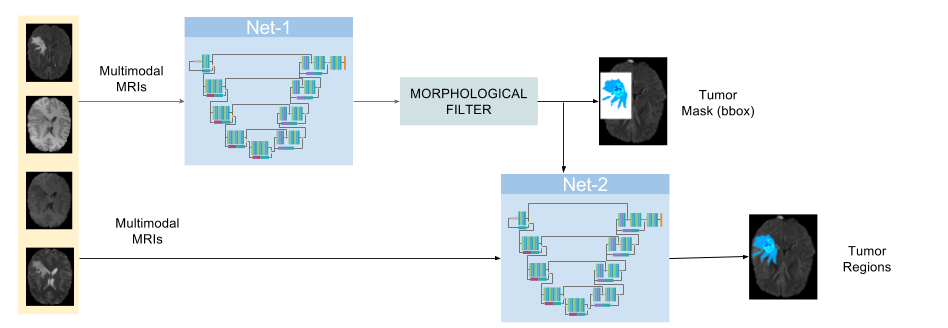

One of the main problems in brain lesion detection is that lesions affect a small portion of the brain, making naive training strategies biased towards the trivial decision of null detection. Brain tumors normally correspond to only 3-5% of the overall image, accounting for 5-15% of the brain tissue and being each tumor region an even smaller portion. To address this issue, we propose to divide the brain tumor segmentation problem into two simpler tasks: (i) segmentation of the overall tumor and (ii) delineation of the different tumor regions. The tasks are performed in parallel using two CNN networks, where the output of the first network is used an input to the second one. The overall system pipeline is depicted in Fig. 1.

2.3 Inference

At inference time, we first get the whole-tumor prediction from the first network. We use morphological filtering to remove small spurious detections made by the first network and we automatically find the smallest rectangular mask that covers the detected tumor. This result is then used as ROI mask in the second network to mask out the majority of false positives, since the second network is only trained to discriminate tumor regions on the vicinity of the tumor. This process can be done in parallel since one can decouple the masking process from the network prediction and thus, save inference time.